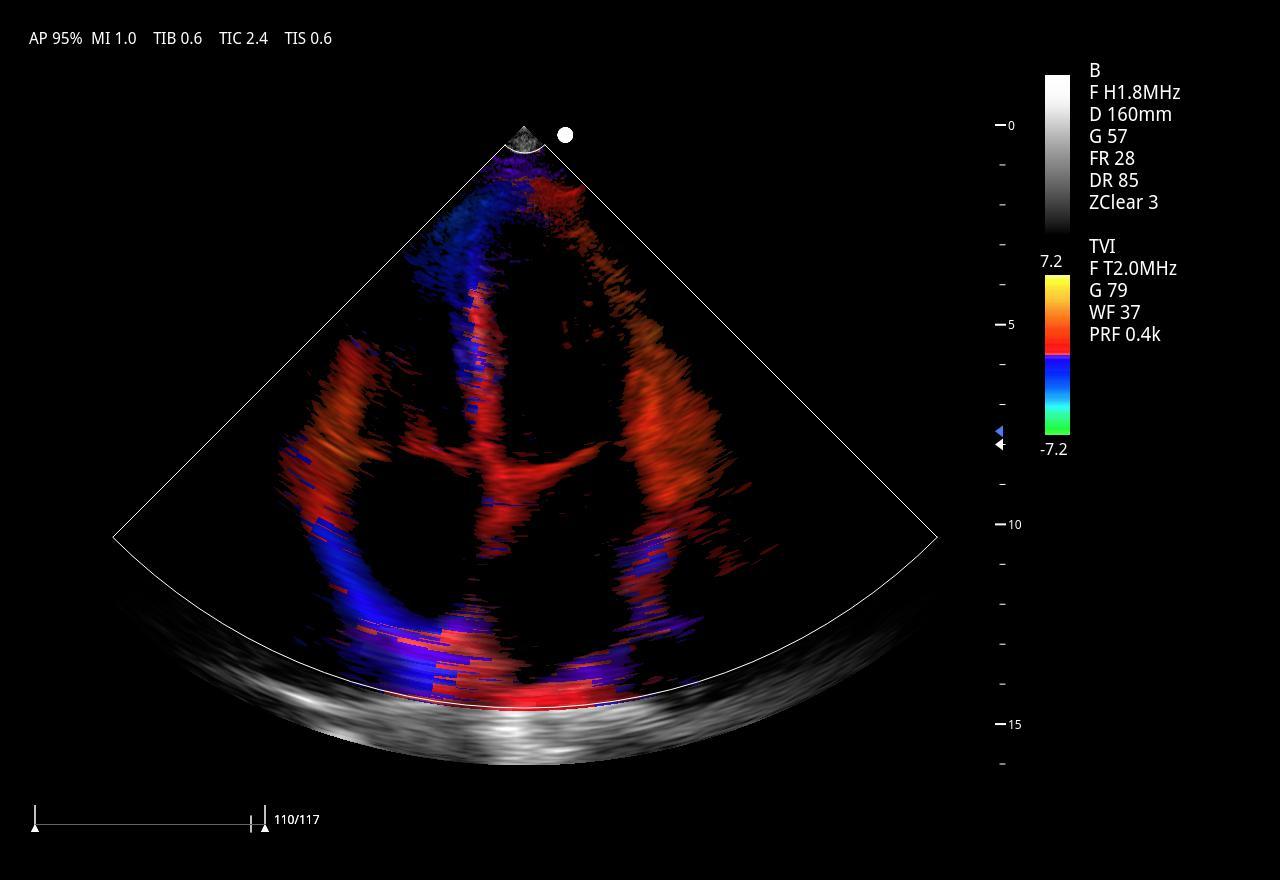

тканевой допплер (TDI)

Секторно-фазированный датчик 3P2PA

• Рабочая полоса частот: 1,0–6,5 МГц

• Количество элементов: 64

• Применение: кардиология взрослых и детей, транскраниальные исследования (TCI), абдоминальные исследования.

Секторно-фазированный датчик 5P1PA